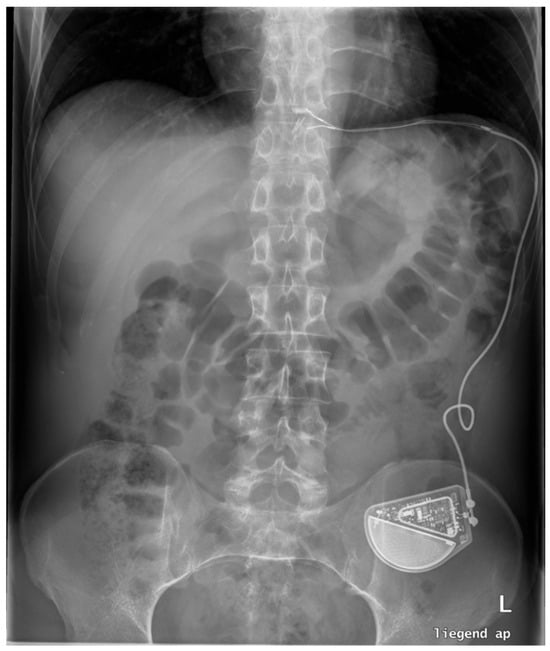

18. Electrical Stimulation (EST)

| MASE | Mucosal Ablation and Suturing |